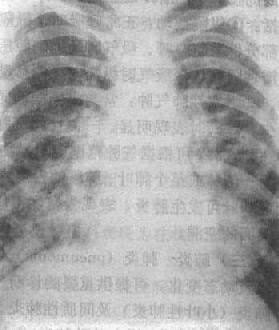

(1)一侧性肺不张:X线现为患侧肺野均匀致密,纵隔向患侧移位,肋间隙变窄(图3-1-7)。健侧肺可有代偿性肺气肿。

图3-1-7 一侧性肺不张

左侧支气管阻塞引起左侧全肺不张,显示左侧肺野均匀致密,

纵隔向患侧移位,肋间隙变窄,膈升高